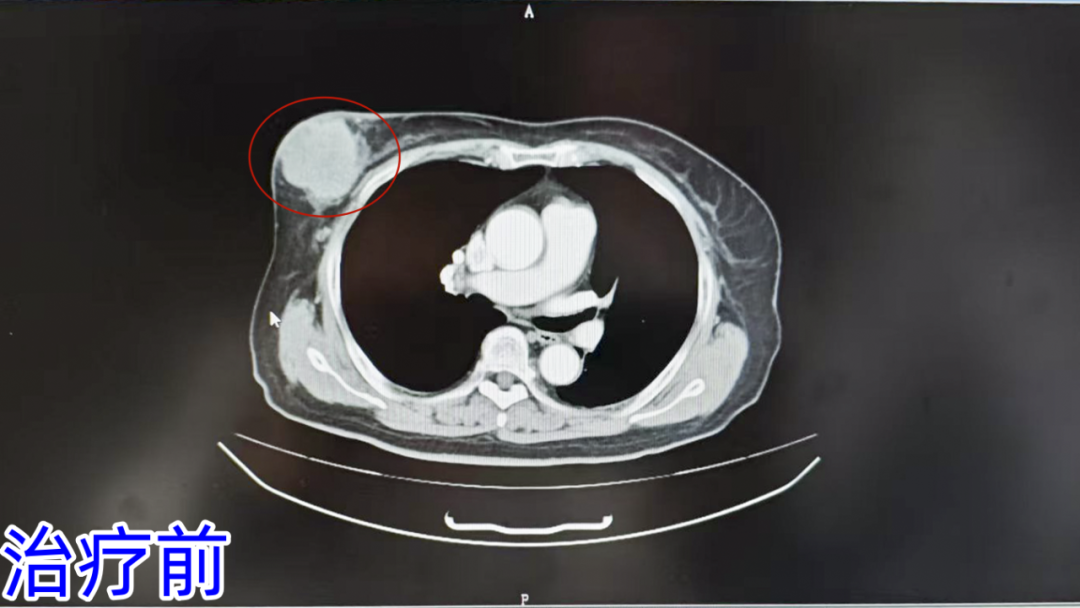

在济南南郊医院的肿瘤科病房里,一位69岁的乳腺癌患者正用笑容诠释着“重生”的意义——5个周期的治疗,70粒放射性粒子的精准植入,一场与时间的赛跑,让生命与希望同频。肿瘤科葛新华主任团队以精准的微创技术为武器,为患者量身定制个性化治疗方案:先后实施DSA引导下的动脉化疗药物灌注术+栓塞术,以及CT引导下碘125放射性粒子植入术。术后仅5周期治疗,肿瘤显著缩小,患者疼痛消失,生活质量大幅提升,家属连赞“技术精湛,服务暖心”。

据了解,2024年7月患者无意间发现右乳出现一肿块,起初并未在意。到了10月,患者自感右乳肿块增大,还伴有胀痛,呈阵发性疼痛,可仍未进行特殊治疗。直至近7天疼痛加剧,患者才意识到问题的严重性,于2024年12月来到济南南郊医院寻求进一步诊治。

为了明确诊断,医院建议行乳腺肿物穿刺活检。在CT引导局麻下,医生顺利完成了乳腺肿瘤穿刺活检术。术后病理结果显示,结合免疫组化符合浸润性导管癌。